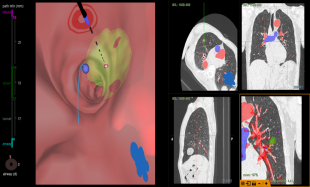

王大伯术前CT

原来,陈恩国主任医师团队运用了最新的BTPNA技术,简单来讲,就是在原有的导航技术上升级了一个经支气管向病灶方向打隧道的办法。 这样,很多原来没有支气管相联通的肺结节,常规导航技术难以到达,现在也可以通过这个技术轻易到达啦! 虽说就是打一条通往结节的隧道,但其中技术含量可没那么简单。要保证安全和准确,术前精密的计算和路径设计非常重要。 王大伯术前,陈主任呼吸内镜介入团队利用最新一代的虚拟导航Lung pro系统对王大伯的胸部CT进行了三维重建,计算出最佳经支气管镜到达病灶的路径,并对手术路径的可行性进行讨论,对可能出现的各种情况进行分析。

术前规划/评估:病灶位置及最佳气道内路径

术中情况

尽管结节比一颗花生大不了多少,但凭借团队医生高超的技术,以及呼吸内镜中心导航系统及DSA的加持,穿刺针穿过管壁,顺利找到了病灶,为了多维度保证位置的准确,介入团队此次利用高大上的锥形束CT进行术中实时定位,确保万无一失。